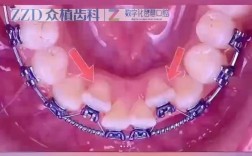

传统金属托槽矫正

这是最经典、应用最广泛的矫正方式,通过金属托槽和弓丝施加力量,移动牙齿,优点是技术成熟、性价比高、适用范围广(几乎所有的错颌畸形都能解决),且力量控制稳定,矫正效率高,缺点是美观性较差,托槽和弓丝明显,可能影响社交时的自信心;口腔舒适度较低,托槽可能摩擦口腔黏膜。